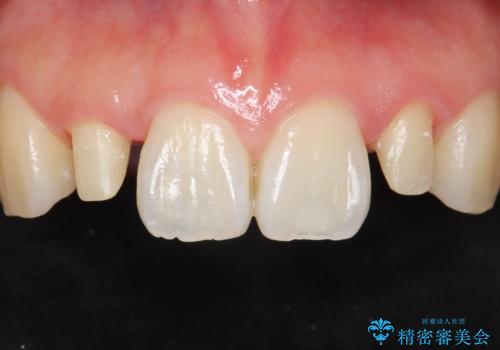

矮小歯 セラミッククラウンで綺麗に 30代女性

全顎的に歯並びにがたつきがあり、上の側切歯(上顎両側2)は生まれつき小さい歯(矮小歯)でした。

矯正治療後、矮小歯をセラミッククラウンにより理想的な歯の大きさに仕上げました。